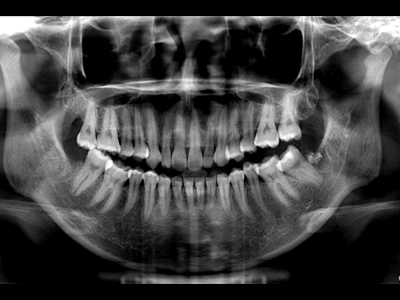

Pro Patient: Our state-of-the-art cone-beam computed tomography (CBCT) technology could selectively image the sinus, oral maxillofacial, para-nasal sinuses, ear & throat regions.

Proactive Dental Management thru our 3D Imaging Manipulation Software

With Oral Maxillofacial CT Scans, your dentist enhances his ability to proactively manage your health concern thru accurate diagnosis & better treatment planning. Moreover, the patient benefits from a painless,low radiation dose CT Scan procedure.